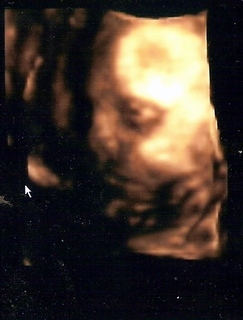

megvolt ma a 4D. Hát a mi kis madarunk elég kis szégyenlős fajta, ismét a lábaival takarta magát, nagyon nehezen tudtunk az arcocskájához férni, de azért sikerült egy-két képet csinálni. Holnap bescannelem, aztán felteszem. Olyan édes volt

Mindenesetre így is látszott a lényeg, hogy fejjel lefelé van, de elég furcsa pozícióban.

A feje van jobbra lent, majdnem középen, aztán a köldökemnél van a háta-hasa-feneke, majd a lába visszafordul a teste elé, egészen le a fejecskéjéig. Szóval olyan kis kifli formában helyezkedik el. Elég érdekes, enyhén jóga-pozitúra